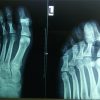

A 32-year-old male patient, attended in the Emergency Room of our Hospital, having sustained a direct injury to the right forefoot while playing soccer. The patient experienced pain in the first toe of his right foot caused by dorsiflexion after kicking the ball. Neurovascular assessment was normal. The simple X-ray revealed hallux IP dorsolateral dislocation (Miki type 2) (Fig. 2a and b). Sesamoid bone interposition manifested after numerous closed reduction attempts without anesthesia and with digital block anesthesia. Closed reduction was attempted under digital block anesthesia. The sesamoid bone interposition was once again observed (Miki Type 1) (Fig. 2c and d).

Dorsal open reduction was achieved by laterally subluxing the extensor hallucis longus tendon and applying pressure to the interposed sesamoid bone toward the plantar aspect of the toe. Due to the medial instability, a Kirschner wire was used to for temporary immobilization of the IP joint with a buddy strapping securing to the second toe for 3 weeks. Fourteen years later, the patient continues to be asymptomatic, participating in normal sporting activities and with symmetrical mobility compared to the healthy contralateral toe.